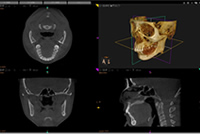

矯正治療の申し込み後、精密検査を行います。患者様の必要なデータを取得し、正式な診断を行います。診断用3D画像を用いて、患者様のための治療計画をデザイン致します。

矯正装置を装着し、治療がスタートします。デジタル矯正システムでは、装置を装着した直後に歯科用CTにて撮影を行い、治療用の3D画像を作成します。(患者様の治療デザインにより撮影の時期は異なります。)

3Dデジタル矯正システムでシミュレーションを行い、最終的な歯の位置を設定し、適切に歯を動かしていきます。

無事に歯列が改善されました。3Dシミュレーションで計画した歯の位置と、実際に移動した位置がお分かりいただけると思います。